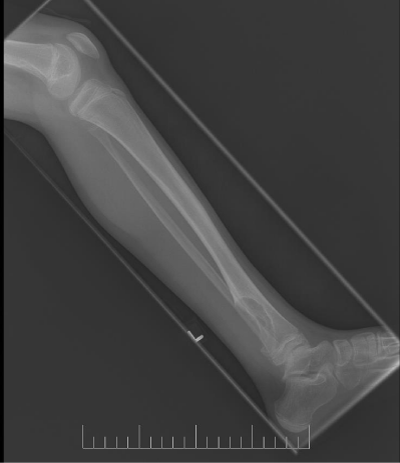

A 10-year-old female presented with left lower leg pain that had progressively increased over the duration of 1 year. On physical examination, tenderness was elicited on palpation of the distal tibia. Routine laboratory testing was normal. X-Ray was performed and revealed a lytic lesion with sclerotic margins in the left lower tibia (Figure 1). MRI was subsequently performed, demonstrating a left lower tibia lesion with low signal intensity on T1 weighted images (Figure 2), and high signal intensity on T2 weighted images (Figure 3). Pathology of the tumor revealed a diagnosis of a CMF. She was treated with curettage and autologous bone grafting (Figure 4). Post op eratively the left leg was immobilized with a plaster cast with restricted weight bearing (Figure 5). Follow up X-ray after 5 years demonstrates no tumor reoccurrence (Figure 6, Figure 7).

Figure 7: 5 year follow up lateral X-ray of the left tibia/fibula.